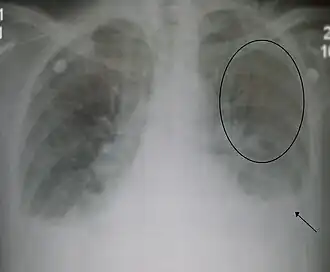

La radiografía de tórax con frecuencia puede asistir en el diagnóstico de una IC. En el paciente compensado, puede mostrar cardiomegalia (agrandamiento visible del corazón), cuantificada como la proporción del tamaño del corazón en el pecho. En la insuficiencia cardíaca izquierda puede haber evidencia de redistribución vascular, líneas de Kerley, pérdida de definición bronquial y edema intersticial.[18]